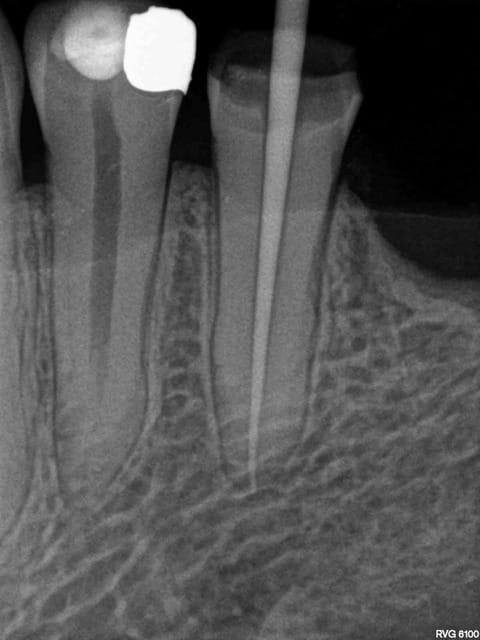

Oui -)))) postes un peu des radios de tes endos micro métrées pour voir.

La radio cone en place était un peu plus sexy. Mais ca ce sont les aléas du système B. Pour 80 boules je ne me fais pas chier à tout reprendre. ( canaux mésiaux en y tu noteras)